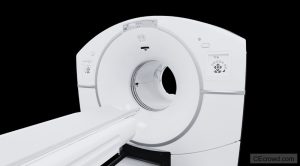

Learn how to maximize the diagnostic value of Cone Beam Computed Tomography (CBCT) while minimizing radiation exposure for safer imaging and smarter decision-making in dentistry.

MRI & CBCT | WHAT DENTISTS NEED TO KNOW